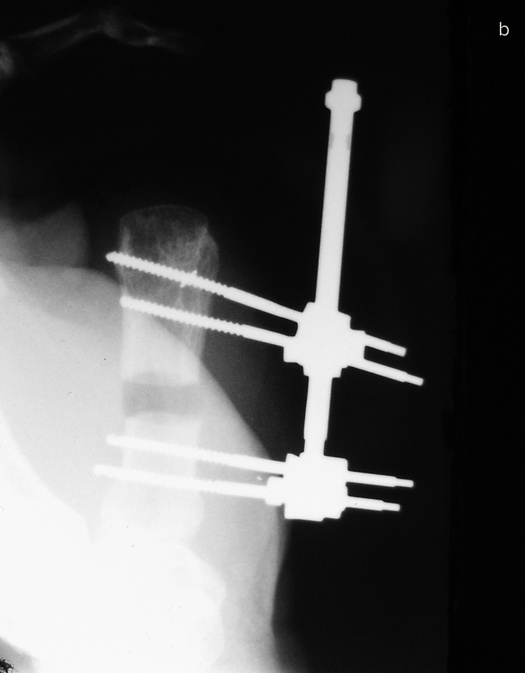

Если восстановить или приживить эту важнейшую часть кисти невозможно, ее реконструируют. Существует три основные методики, которые я условно называю «упросить», «одолжить» и «украсть». В первом случае хирург и пациент как бы упрашивают обрубок большого пальца вырасти в длину. С обоих концов оставшейся кости хирург вставляет поперечные стальные шпильки, прикрепляет эти шпильки к стальной раме и разрезает кость между ними.

Пациент каждый час поворачивает небольшую ручку этого приспособления, напоминающего аппарат Илизарова, и по чуть-чуть увеличивает промежуток между фрагментами кости. Процедура длится от шести до восьми недель. Кость и окружающие ее мышцы, сухожилия, нервы и кожа едва ли понимают, что их растягивают: для них это просто какой-то очень быстрый рост, и им надо успеть.

Когда большой палец вновь обретает рабочую длину, хирург заполняет промежуток костным трансплантатом. Преимущество такого способа удлинения в том, что не приходится ничего «одалживать» или «красть». Однако не все так радужно: ноготь и отсутствующие суставы большого пальца уже не вернуть.